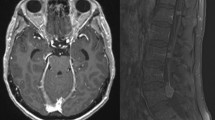

Leptomeningeal metastases (LM) represent an aggressive, advanced stage of cancer with substantial neurologic morbidity and a grim survival of 2–5 months [1, 2]. Also known as leptomeningeal carcinomatosis or neoplastic meningitis, LM occurs when cancer cells gain access to the cerebrospinal fluid (CSF) that surrounds the brain and spinal cord, either through hematogenous dissemination via the choroid plexus, retrograde venous extension, or direct seeding from parenchymal metastases across the glia limitans [3,4,5]. Upon entry, LM adopts two phenotypic states: adherent plaques to the brain and spinal cord visualized with contrast-enhanced magnetic resonance imaging (MRI), and free-floating cells within the spinal fluid detected via CSF cytology [6]. As such, diagnosis and surveillance of LM require full neuraxial MRI and CSF analysis to fully stage the burden of disease [7, 8]. The estimated incidence of LM from systemic malignancies is approximately 5–20% based on population and autopsy data [9,10,11,12]; the true incidence of LM is likely higher owing to insensitivity of CSF cytology and asymptomatic leptomeningeal seeding [13].

Conventional treatment of LM includes intrathecal chemotherapy for those with adequate performance status, whole brain radiation therapy (WBRT) to cranial disease and/or involved-field radiation therapy (RT) to disease of the spinal cord and cauda equina, and systemic chemotherapies with adequate central nervous system (CNS) penetration (Fig. 1). Symptoms referrable to increased intracranial pressure can be ameliorated with palliative ventriculoperitoneal shunting [14]. For those without abnormal CSF flow dynamics, commonly used intrathecal therapy options include methotrexate [15,16,17], thiotepa [18], and topotecan [19]. No single intrathecal chemotherapy has emerged as providing a significant survival benefit, and their use is associated with increased neurotoxicity risk [20,21,22].

Anatomic considerations and conventional therapeutic strategies for leptomeningeal metastases. This illustration outlines the two phenotypic states of leptomeningeal metastases (LM), existing as both free-floating disseminated cells and adherent plaques to the brain and spinal cord. The three pillars of conventional therapies are shown, including intrathecal therapy (blue dots) through an Ommaya reservoir, systemic therapy (yellow dots) entering the cerebrospinal fluid (CSF) via the blood-CSF barrier of the choroid plexus, and involved-field radiation therapy (yellow beam) directed here against the adherent cells of the conus medullaris and cauda equina